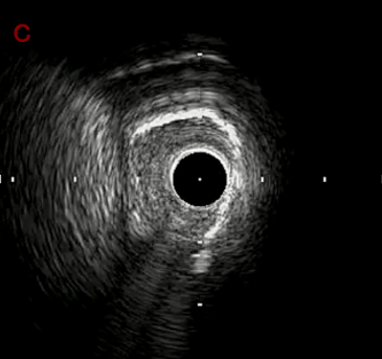

IVUS after OAS high speed 3回追加

IVUS imaging after high speed 3回追加

a,b,cの十分な石灰化のsanding。

High riskのbias所見へと変わっていったdの部位に関してはpinpoint OASを行うことでinjuryなく治療できた。

Cutting + DCBの方針に。